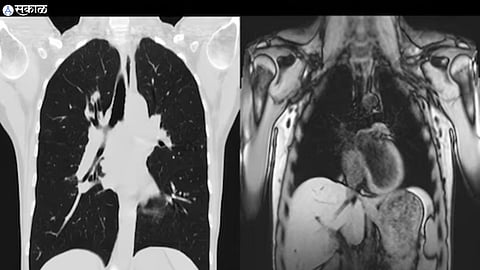

शरीराच्या आतील बदल पाहण्यासाठी आणि फोटो घेण्यासाठी एमआरआय चुंबकीय आणि रेडिओ लहरींचा वापर करते. सॉफ्ट टिश्यू इमेजिंगसाठी ही चाचणी अधिक चांगली आहे. सामान्यतः मेंदू, मणक्याचे आणि अवयवांच्या तपशीलवार तपासणीसाठी वापरलं जातं. याशिवाय, सांधे, मेंदू, मनगट, घोटा, छाती, हृदय आणि रक्तवाहिन्या तपासण्यासाठी देखील याचा वापर केला जातो.

सीटी स्कॅन म्हणजे संगणित टोमोग्राफी स्कॅन. हे देखील एक वैद्यकीय इमेजिंग तंत्र आहे. हे आपल्या शरीरातील अवयवांच्या छोट्या छोट्या प्रतिमा घेऊन त्यांचा अभ्यास करण्यास मदत करते. हा एक प्रकारचा त्रिमितीय एक्स रे आहे. या स्कॅनमध्ये, एक्स रे आणि कम्प्युटरच्या मदतीने आपल्या शरीराच्या क्रॉस सेक्शनल प्रतिमा तयार केल्या जातात, ज्यामुळे शरीरात विकसित होणारा रोग समजण्यास मदत होते.

सीटी स्कॅन हाडं तपासण्यासाठी अधिक चांगले असतात आणि अनेकदा आपत्कालीन परिस्थितीत वापरले जातात. हे एक्स रेच्या अधिक तपशीलवार आणि स्पष्ट प्रतिमा प्रदान करते. एमआरआय आणि सीटी स्कॅन वेगवेगळ्या इमेजिंग तत्त्वांवर काम करतात. एमआरआय आपल्या शरीरातील फोटो घेण्यासाठी चुंबकीय आणि रेडिओ लहरींचा वापर करतो. तर सीटी स्कॅनमध्ये, एक्स रेचा वापर शरीरातील अवयवांच्या क्रॉस सेक्शनल प्रतिमा तयार करण्यासाठी केला जातो.